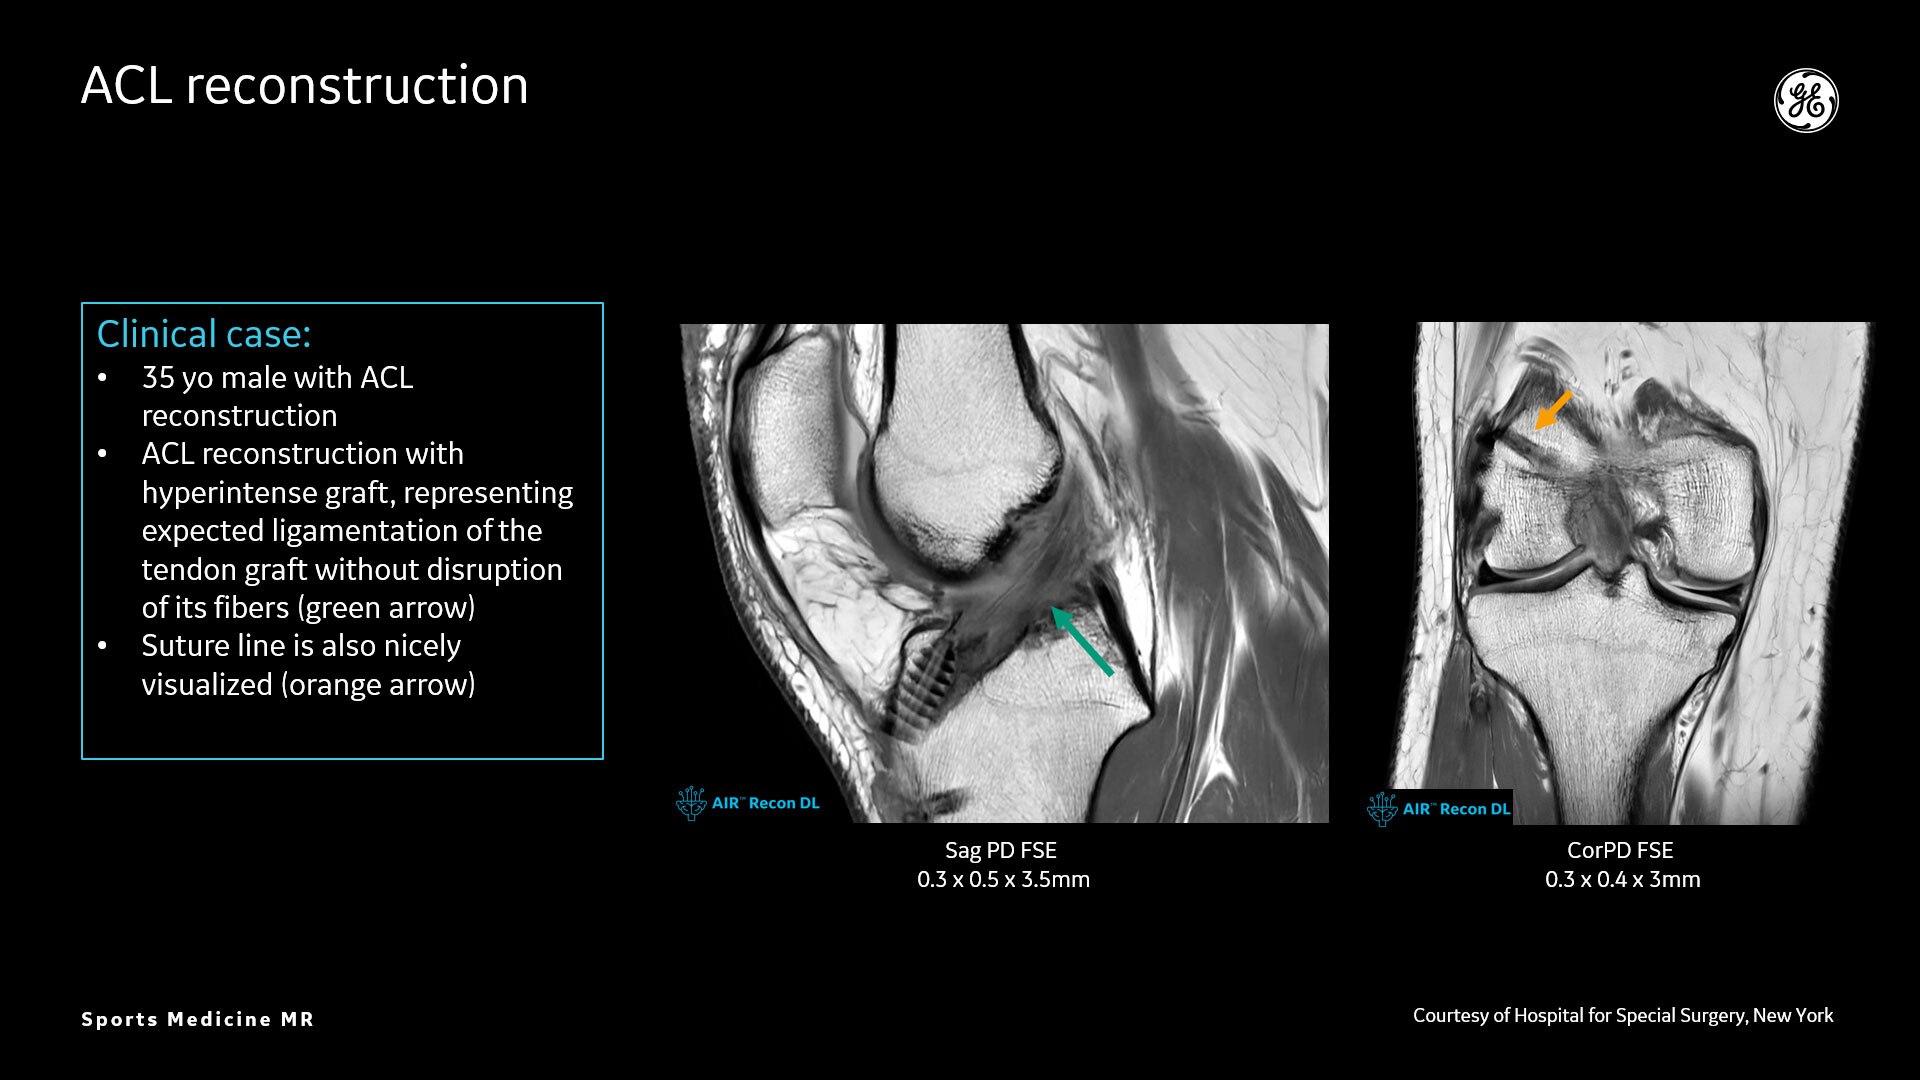

AIR™ Recon DL provides high-resolution images with increased SNR at markedly reduced scan times. This technology optimizes the depiction of even small injuries, such as meniscal, labral and ligament tears. The reduction in scan times increases flexibility for individually tailored MR protocols with an additional oZTEo sequence for detailed fracture assessment.